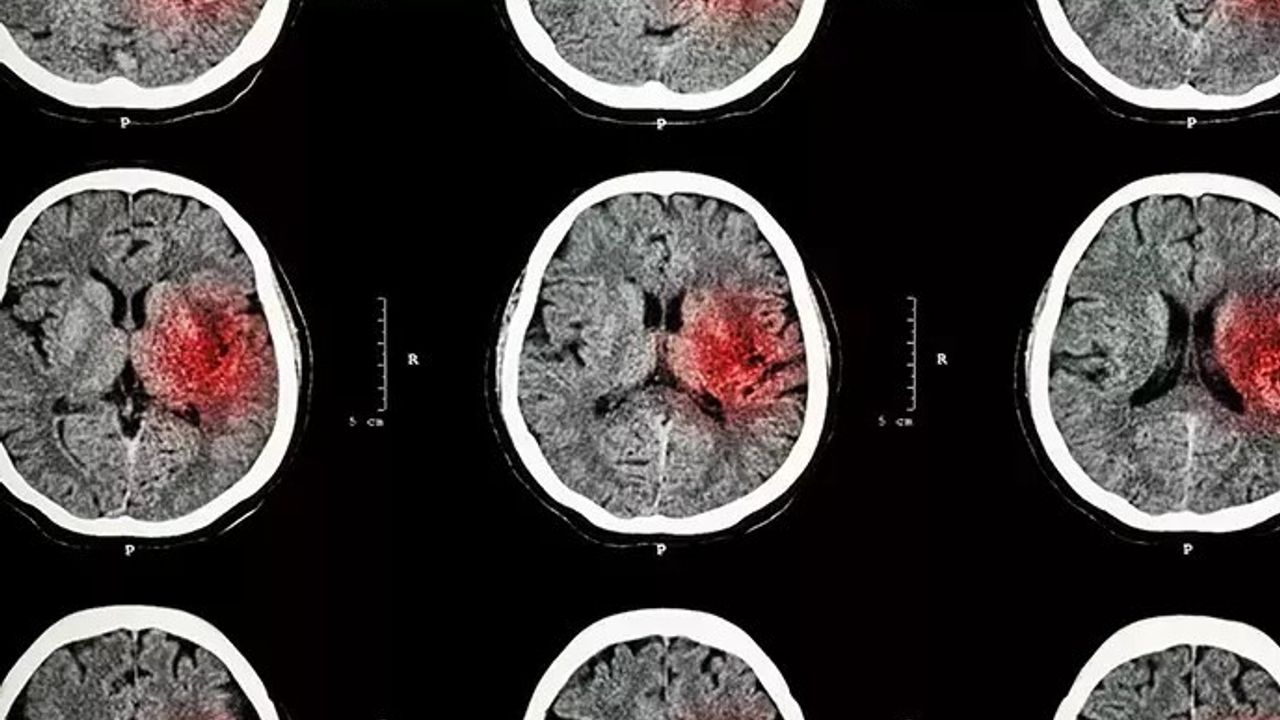

İnmenin iskemik inme ve hemorajik inme olarak iki türü bulunduğundan bahseden Nöroloji Uzmanı Dr. Hikmet Dolu, "İskemik inme en sıklıkla görülen inme türüdür. Beynin kan damarlarındaki daralmadan veya tıkanmadan dolayı meydana gelmektedir. Hemorajik inme ise, beyindeki bir kan damarının yırtılması durumunda meydana gelmektedir. Siz ya da çevrenizdeki bir kişi inme geçiriyorsa, semptomların başladığı ana dikkat etmek çok önemlidir. Çünkü bazı tedavi teknikleri, felcin hemen ardından uygulandığında etkili olabilmektedir" dedi.